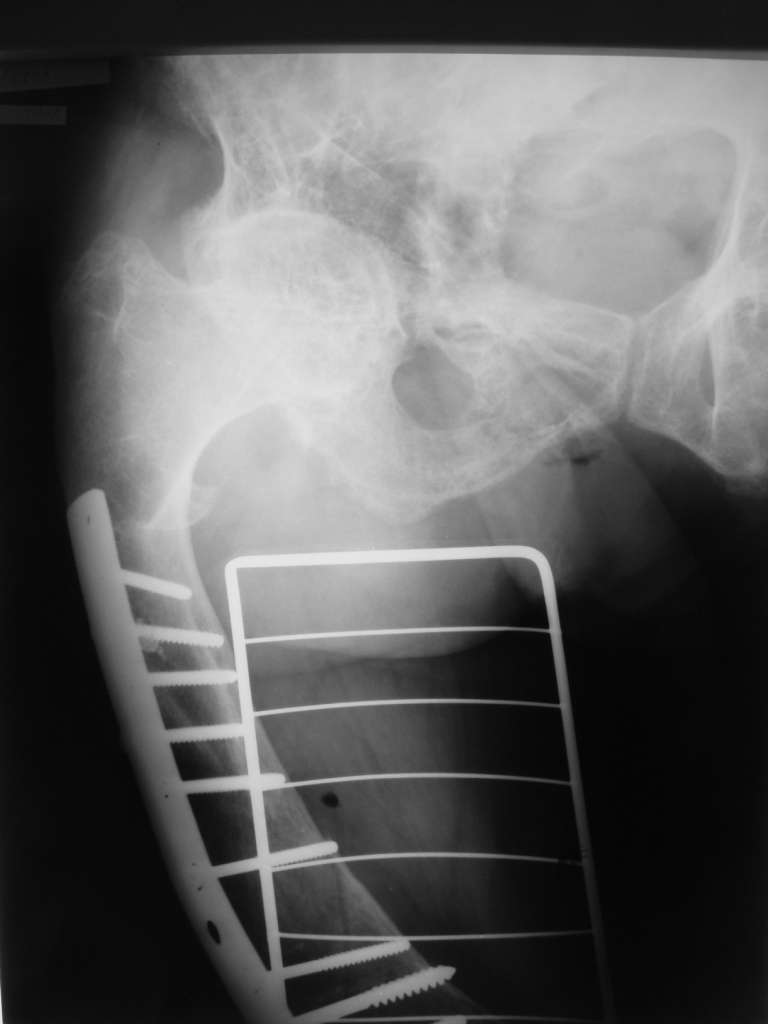

Травма в результате ДТП. (Пациентка передвигалась на инвалидной каляске и была сбита автомобилем). Диагноз: Множественная травма. Перелом нижней трети правого бедра. Перелом средней трети правой б/берцовой, малоберцовой кости, нижней трети левой большоберцовой, м/берцовой кости.Травматический шок. Со стороны внутренних органов и систем без патологии. Больная госпитализирована в реанимационное отделение, где было наложено двойное скелетное вытяжение за правую н/конечность. Левая н/конечность иммобилизована гипсовой лонгетой.

Из анамнеза: больная является инвалидом 1 группы по опорно-двигательному аппарату. В детстве перенесла рахит. Осложнением которого "О" образная деформация нижних конечностей. Ограничено отведение нижних конечностей, деформирующий артроз тазобедренных и коленных суставов. В 1990 году перелом правого бедра остеосинтез пластиной. После операции больная передвигалась только на костылях или в инвалидной коляске.

Прошу прощения за качество снимков. Р-графия производилась в реанимационном отделении передвижным аппаратом.